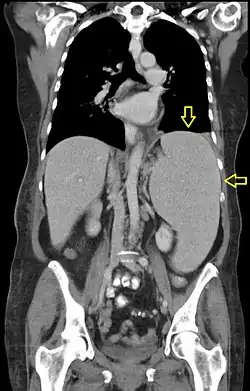

Hepatosplenomegalia – termin medyczny oznaczający powiększenie wątroby i śledziony.